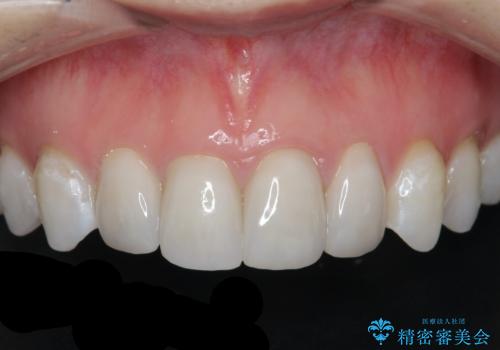

[ セラミック治療 ] 前歯の変色をきれいにしたい

担当医 大元洋佑

![[ セラミック治療 ] 前歯の変色をきれいにしたいの症例 治療前](https://seimitsushinbi.jp/wp/wp-content/uploads/2023/12/8095b301c8ea19cbf7179d372450bebf-500x350.jpg?v=1703129532)

![[ セラミック治療 ] 前歯の変色をきれいにしたいの症例 治療後](https://seimitsushinbi.jp/wp/wp-content/uploads/2023/12/528aed1286d6fd20e773cd5dfb0c7971-500x350.jpg?v=1703129602)